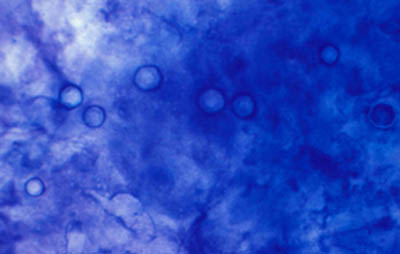

Frotis - extendido en capa

Preparaciones de extendido en capa sobre laminilla con agua destilada sin colorear, en campo claro y bajo contraste de fases: permite buena visualización de las formas Quísticas de Acanthamoeba

Magnificación 160x

Tinción CW

Blanco de Calcofluor + Azul de Evans

Tinción Giemsa

Tinción PAS

(Acido Periodico de Schiff)